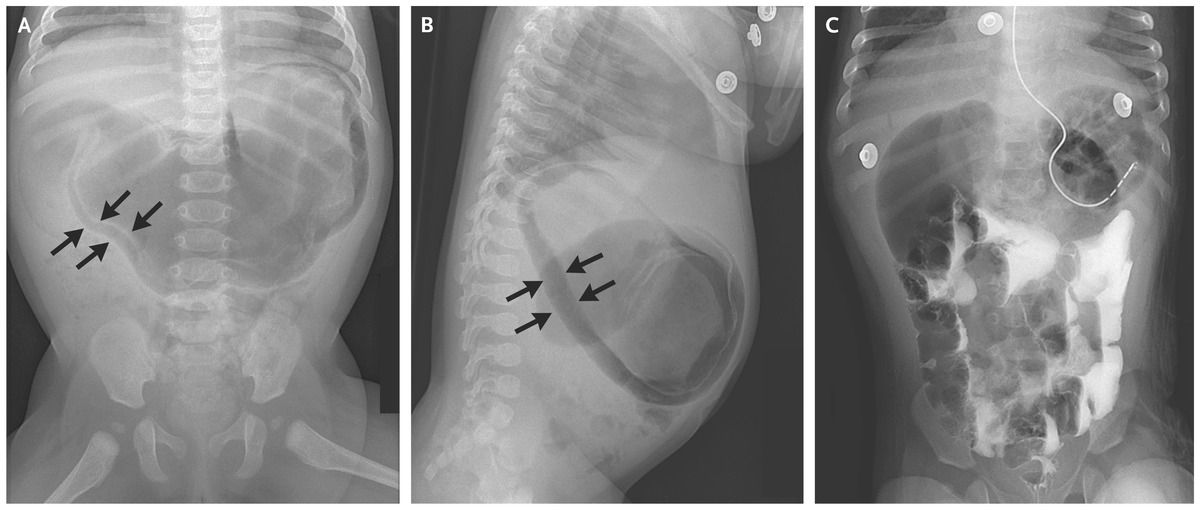

A nasogastric tube was placed, and intravenous administration of fluids was started. Radiography of the upper gastrointestinal tract with contrast revealed contrast medium passing into the small intestine; follow-up images showed resolution of pneumatosis and a “double bubble,” which suggested duodenal obstruction (Panel C).

Duodenal obstruction caused by a duodenal web was identified intraoperatively, and a duodenoduodenostomy was performed, which resulted in resolution of symptoms.